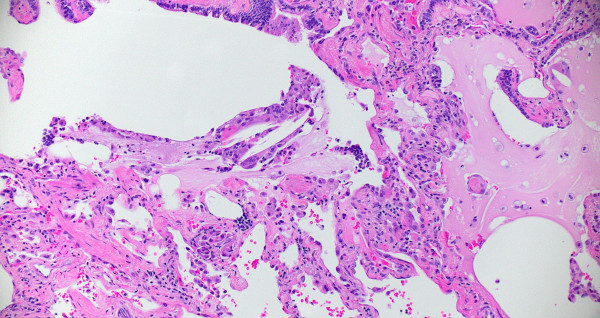

Compute tomography (CT) scan of the chest showed subpleural and peribronchial fibrosis with air-trapping on expiratory phase. The findings were read as likely “non-IPF pattern.” A serum antibody panel for hypersensitivity pneumonitis was positive for antibodies to Aspergillus flavus. Histologic sections of her lung biopsy demonstrated airways with peribronchiolar fibrosis with extensive metaplastic changes (Figure 1). Intra-alveolar giant cells and histiocytes with cholesterol clefts were seen (Figures 2-3). There were areas of interstitial inflammation and fibrosis resembling a cellular non-specific interstitial pneumonia (NSIP) pattern of injury (Figure 4). Also seen were extensive peribronchiolar metaplasia, microscopic “honeycombing”, interstitial giant cells, and poorly-formed granulomata (Figures 5-7).